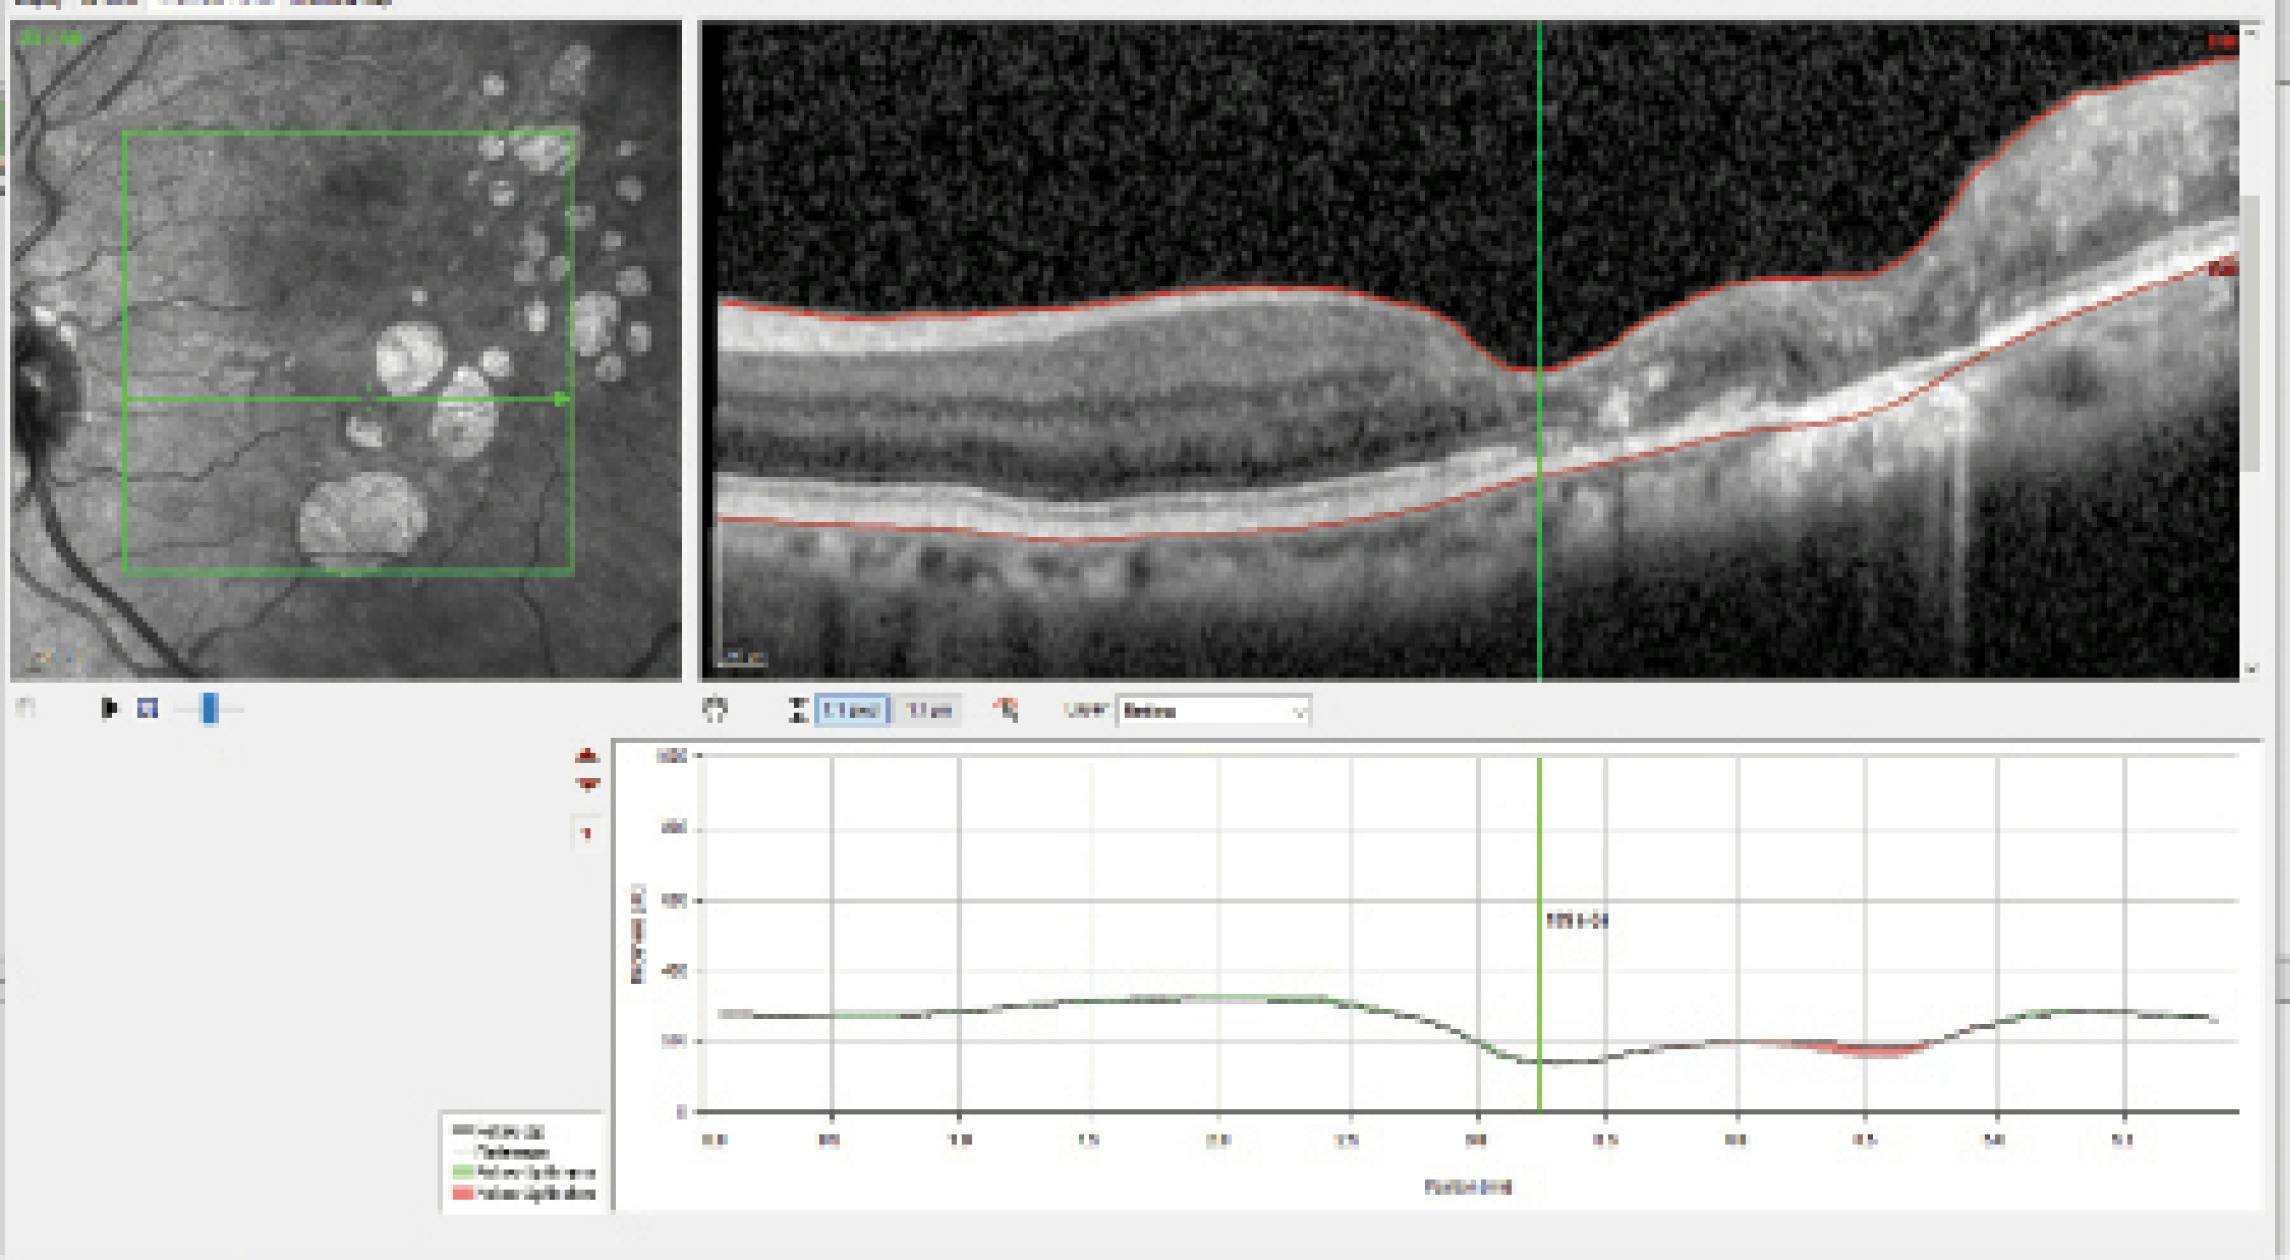

Dr. Radcliffe: The patient does not undergo cataract surgery then but returns 1 year later. At this point, a new lesion has developed, more atrophy is present, and quality of vision has decreased due to cataract progression (Figure 2). The patient is interested in surgery. Dr. Kitchens, with the new treatment options for GA, how should this conversation go?

Dr. Kitchens: As mentioned above, there is a wide spectrum of referring doctors, and comfort levels vary. If you keep up on technology, like to prepare your patients, and have a good communication strategy with your retina colleague, then talk to this patient about their GA. You can tell them, “This is where you were then, and this is where you are now. You have geographic atrophy. New treatments are available, and, although they cannot improve your vision, they will help slow down the disease. Therapy involves an injection given by a retina specialist.”

Also, this patient is likely already having difficulty reading and will say that they are missing parts of words. I would love to have caught them at the previous scan or even prior.